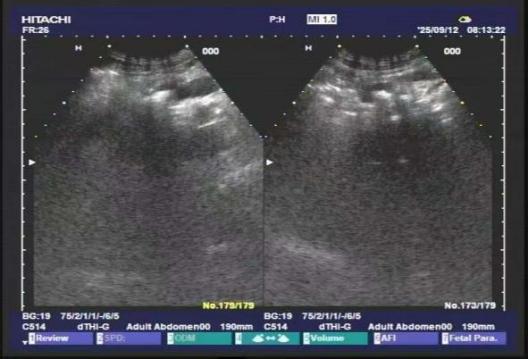

这些藏在翟先生体内的顽石,不仅体积巨大,而且位置极度刁钻。如果采用开腹取石的传统手术方式,非但创伤面积难以缩小,更存在其他伴生风险。本着不给翟先生增加痛苦与负担的初衷,普外一科联合碎石中心、手麻科和功能科举行多学科联合评估。得益于功能科与影像科的精确定位,翟先生体内结石大小、位置与胰管情况被精准捕捉,在反复推敲病情后,普外一科最终决定创新治疗思路,在咸阳市首次采用“体外冲击波碎石+后续内镜取石”的个体化微创治疗方案,这也是我院体外冲击波碎石技术,在泌尿系结石等常规治疗外,打击范围的再度扩张。

术后的超声复查显示,胰管内结石已被成功击碎,胰管明显通畅,患者状态恢复平稳,未出现胰腺炎急性发作等并发症,现已顺利返回病房。